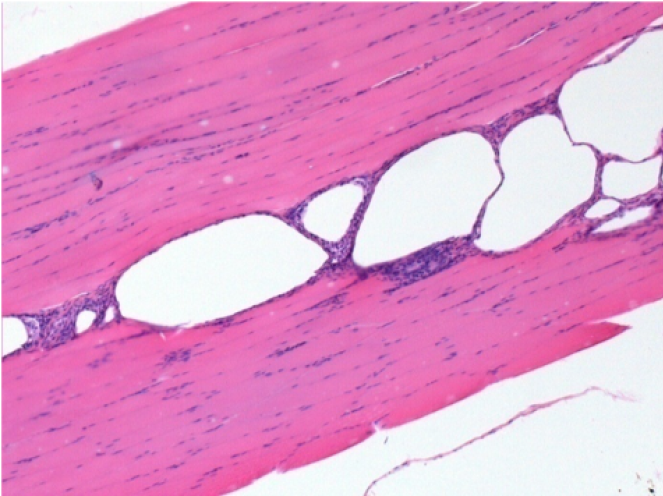

3 months after Endopeel Injection

3 months (D90)after Endopeel Injection 0.1ml in the right pretibial muscle.

L : Control-100xD90

R:100xD90